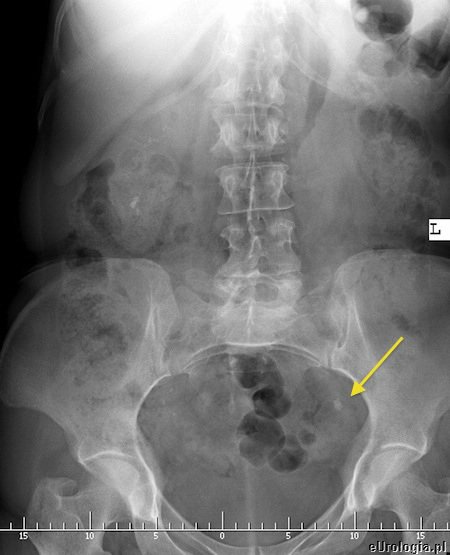

Ustalenie lokalizacji złogu w moczowodzie czasami bywa trudne w warunkach ambulatoryjnych. W przypadku podmiedniczkowego i śródściennego odcinka moczowodu czasami udaje się uwidocznić złóg w czasie USG jamy brzusznej. Złogi uwapnione w większości przypadków widoczne są na zdjęciu przeglądowym jamy brzusznej. Aby dokładnie uwidocznić kamień i ustalić czy cienie mogące być uwapnionymi złogami na zdjęciu zlokalizowane są w moczowdzie należy wykonać urografię lub tomografię komputerową. Czasami konieczne jest ustalenie lokalizacji złogu wykorzystując pielografię zstępującą - u pacjentów z przetoką nerkową - nefrostomią lub pielografię wstępującą.

Fot. Zdjęcia przeglądowe jamy brzusznej pacjentów z kamicą moczowodową. strzałkami zaznaczono złogi w moczowodach.